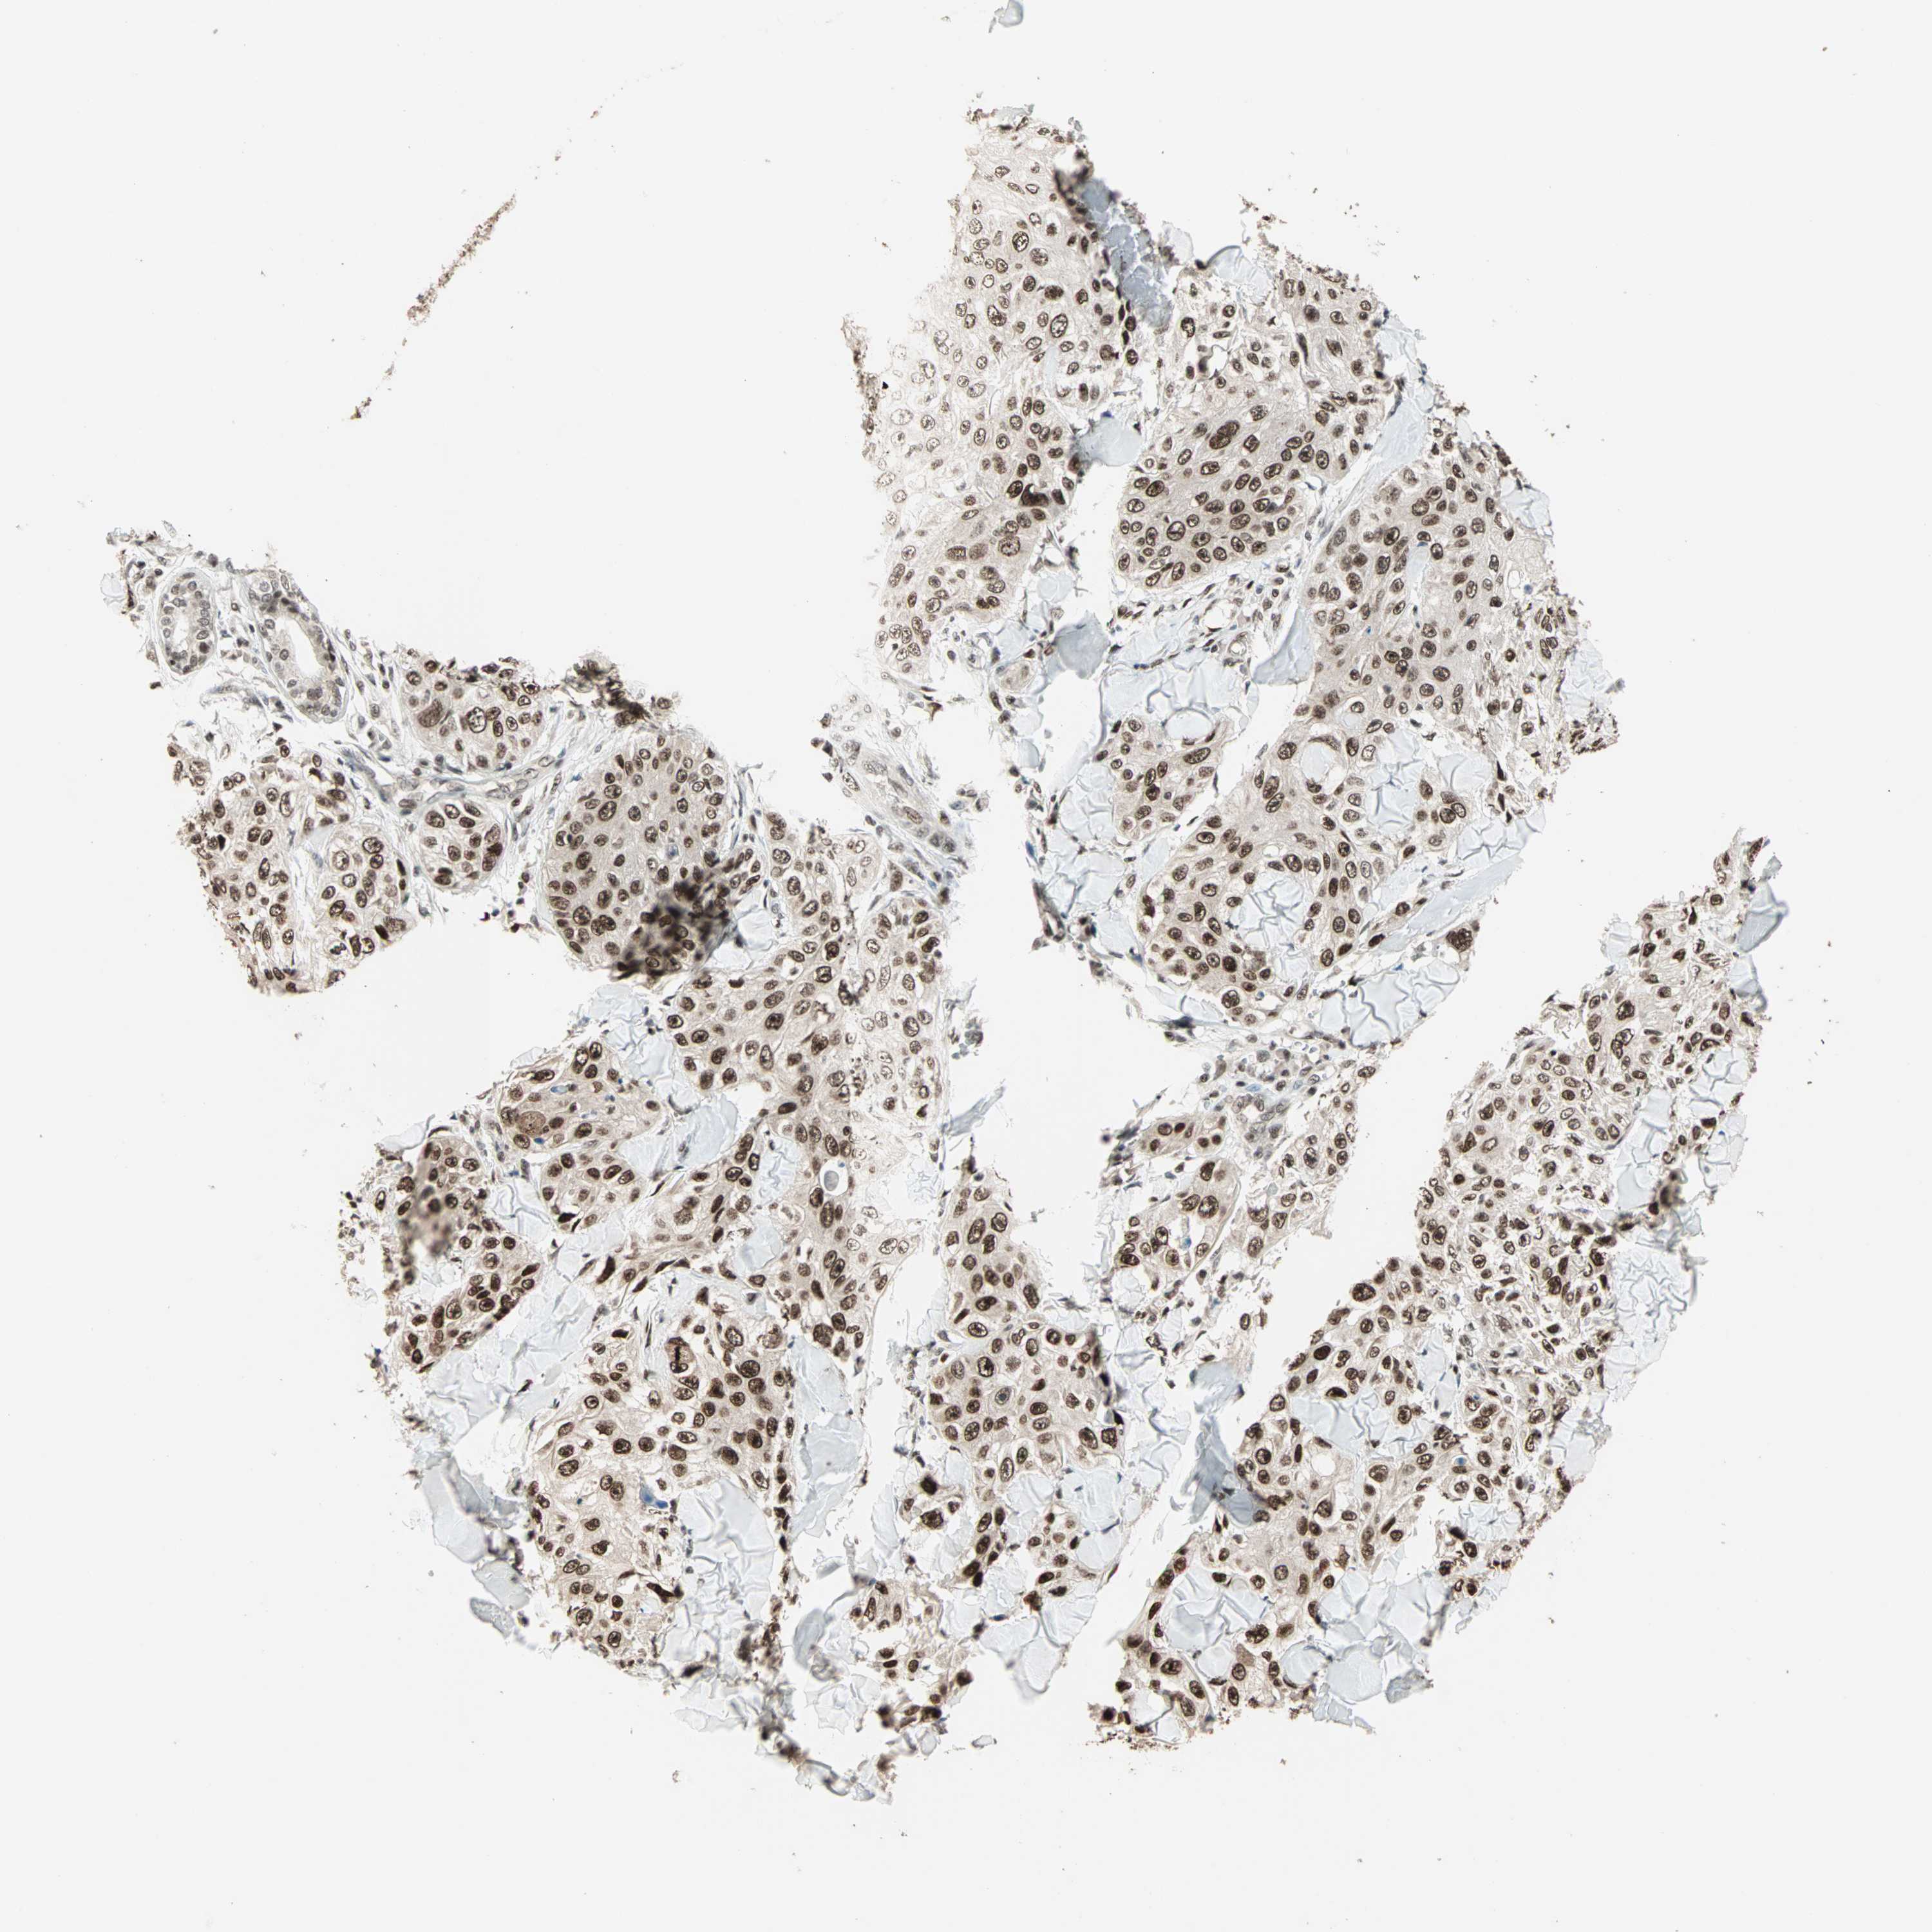

SKIN CANCER - Protein expressioni

A mouse-over function shows sample information and annotation data. Click on an image to view it in a full screen mode. Samples can be filtered based on level of antibody staining by selecting one or several of the following categories: high, medium, low and not detected. The assay and annotation is described here.

Antibody stainingi

Antibody staining in the annotated cell types in the current human tissue is reported as not detected, low, medium, or high, based on conventional immunohistochemistry profiling in selected tissues. This score is based on the combination of the staining intensity and fraction of stained cells.

Each image is clickable and will lead to virtual microscopy that enables deeper exploration of all samples and also displays staining intensity scores, fraction scores and subcellular localization as well as patient and tissue information for each sample.

Antibody HPA006915

Staining

Low

Intensity

Weak

Quantity

<25%

Location

Nuclear

Papilloma, NOS